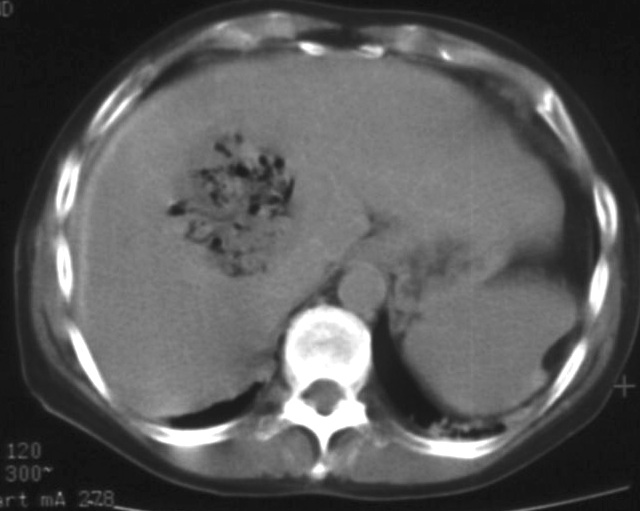

Figure 27. – US and CT examinations before percutaneous ethanol sclerotization (A: US examination, B: CT examination)

The puncture of the cyst is usually guided with US (rarely with CT). The puncturing needs to take place from the parenchymal side of the cyst. When its contents are removed the empty cavity is filled up with diluted contrast material to ensure that there is no contrast leakage to the surroundings. The 96% ethanol is only injected after the contrast material has been removed and no leakage was found. (The volume of the alcohol should not exceed 50-60% of the cyst or 100 ml.)

The injected ethanol is left in the cyst for 20 minutes. Following this, the alcohol is drained as well. Cystic regression is then regularly controlled with US or CT examinations. (Figures 28., 29.) Patient complaints usually cease within 4-6 weeks after the treatment.

Image

Figure 28. – Control CT examination after percutaneous ethanol liver cyst sclerotization (9 months later) – significant regression

A

B

Figure 29. – Percutaneous ethanol hepatic cyst sclerotization, CT examinations (A: before treatment, B: 6 months after treatment ) – pronounced regression